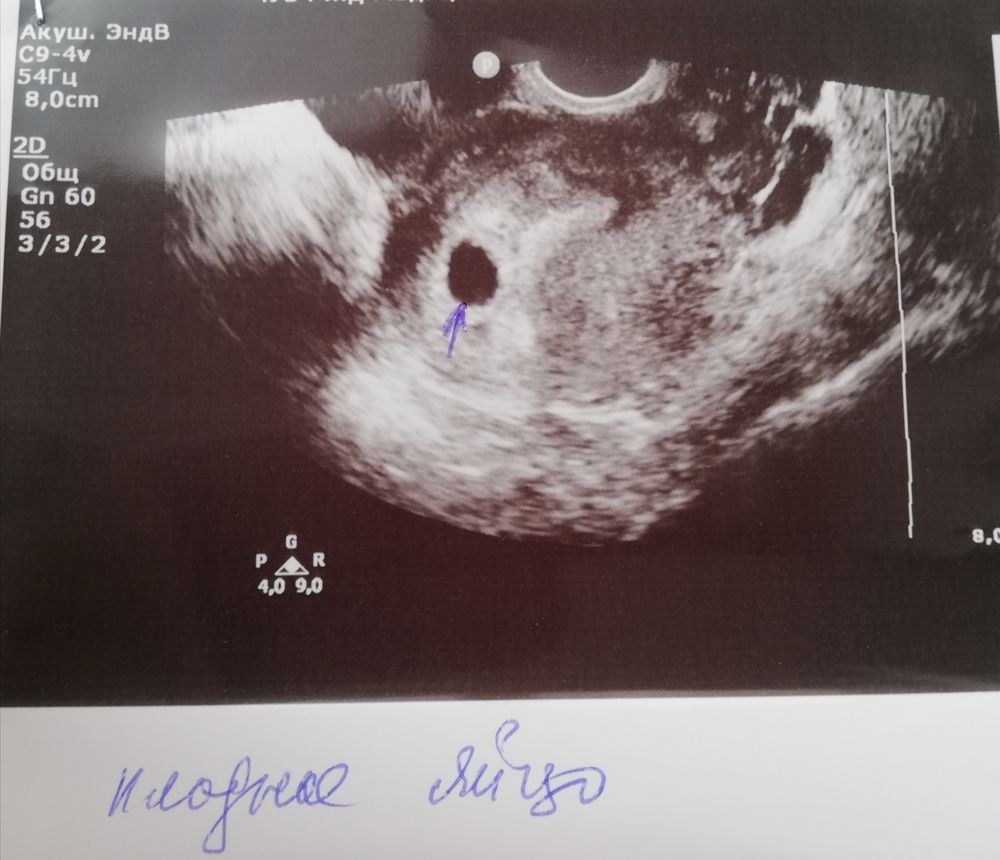

У меня 6 неделя по последним месячным. Сегодня сходила на первое узи. Оно мне почему то показалось немного странным. Не знаю почему.У нас в городе не так много где делают узи. Пошла на первое попавшееся.

Сказал все хорошо, написала 5 недель, говорит сердцебиение пульсируется и все ок. Но она особо долго не искала, все сразу записывала

И размер эмбриона 2.5 мм. И сдала сегодня хгч. Завтра результат, посмотрим как там дела

Результаты узи ниже.